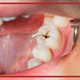

درمان ریشه دندان یا همان عصب کشی دندان نیز همواره به عنوان یک روش ترسناک در میان بیماران شناخته میشود. اما علت این ترس چیست و از کجا نشات میگیرد؟ در این مقاله قصد داریم رایجترین افسانهها و شایعاتی را که درباره درمان کانال ریشه دندان وجود دارد با هم مرور کنیم تا به بیماران ثابت کنیم که هیچ یک از این افسانهها حقیقت نداشته و نیازی به ترسیدن نیست.

باور غلط شماره 1: "درمان کانال ریشه دندان یک درمان بسیار دردناک است."

زدن این حرف در دنیای پزشکی امروز و با استفاده از فناوری و داروهای بیحسی مدرن و پیشرفته کمی خنده دار به نظر میرسد. دندان پزشکان تلاش میکنند تا با استفاده از مقادیر کافی از داروهای بیحسی و تسکین دهنده تا حد امکان درمان کانال ریشه را به یک فرایند بدون درد تبدیل کنند. به همین دلیل و با وجود این درمانهای مدرن، درمان کانال ریشه میتواند به اندازه پر کردن حفره دندان بدون درد انجام شود.

درد دندان بیشتر به دلیل آسیب بافتی داخل دندان ایجاد میشود. یک دندانپزشک متبحر میتواند با استفاده از درمان کانال ریشه به راحتی این درد را از بین ببرد. تمام تلاش یک دندان پزشک این است که تا حد امکان درد شما راکاهش داده و دندان های طبیعی شما را حفظ کند. بنابراین نیازی نیست که از بابت درد نگران باشید زیرا که دندانپزشکان در مدیریت درد شما در حین درمان متبحر هستند.